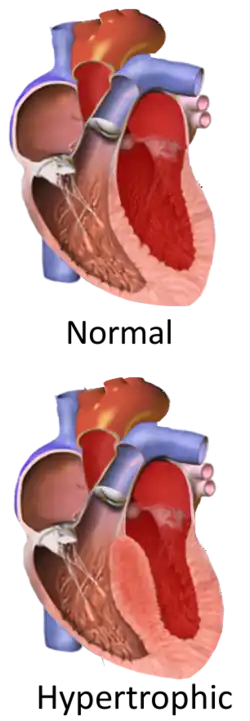

Hypertrophic cardiomyopathy (HCM, or HOCM when obstructive) is a condition in which muscle tissues of the heart become thickened without an obvious cause.[8] The parts of the heart most commonly affected are the interventricular septum and the ventricles.[10] This results in the heart being less able to pump blood effectively and also may cause electrical conduction problems.[3] Specifically, within the bundle branches that conduct impulses through the interventricular septum and into the Purkinje fibers, as these are responsible for the depolarization of contractile cells of both ventricles.[11]